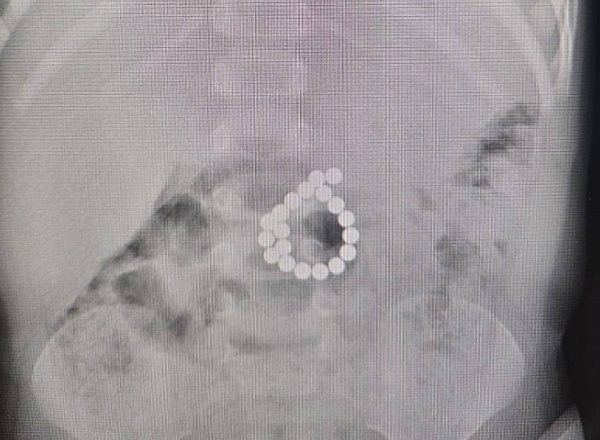

Редкий диагноз, сложная операция и спасение через соцсети: как Нижневартовская ОКБ помогла девушке из Екатеринбурга

В Нижневартовской окружной больнице прооперировали 19-летнюю девушку из Екатеринбурга с редким диагнозом — врожденным семейным аденоматозным полипозом. Это заболевание сопровождается образованием множественных полипов в кишечнике с высоким риском перерождения в злокачественные опухоли. Об этом сообщил глава депздрава ХМАО Роман Паськов. Когда опасные новообразования обнаружили еще и в луковице двенадцатиперстной кишки, семья столкнулась с проблемой поиска специалистов, готовых взяться за такой непростой случай. Помогли социальные сети. Мама пациентки увидела в паблике Нижневартовской ОКБ историю девушки с похожим диагнозом и успешным результатом. Она связалась с врачом и сразу прилетела на лечение. Нижневартовские врачи не подвели. Несмотря на техническую сложность (тонкие стенки, труднодоступное расположение полипов), операция прошла без осложнений. Пациентка уже восстанавливается под наблюдением специалистов.